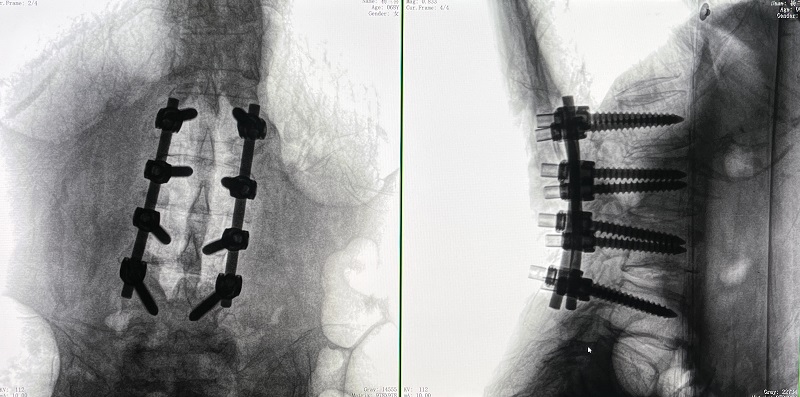

機(jī)器人輔助腰椎后路側(cè)彎矯形手術(shù)術(shù)前圖像

術(shù)前圖像